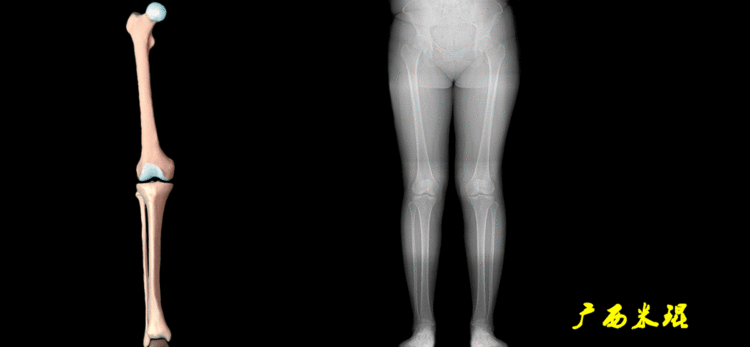

下肢力线及相关角度测量的前提是必须拍摄标准的站立位也就是负重位的下肢全长片。目前这样的照片都是放射科的技师在电脑上拼接出来的,大部分医院的DR都能够做到这一点。

患者直立于摄影架上,后背贴近摄影架,双手自然下垂,膝关节尽量伸直,足部与双肩同宽,要求投照时双髌骨朝正前方,通常患者双足尖应平行向前即可。

提醒一下大家,拍摄过程中应避免下肢的外旋和内旋。如果有一侧肢体短缩时,投照应当用脚垫垫高短缩肢体,使骨盆保持水平,这样下肢短缩测量才精确。如果有肢体旋转畸形时,还是以髌骨朝前为标准,虽然此时双足可能不能保持平行。

二、下肢全长片的基本要求

无论如何,拍摄出来的下肢全长片必须包含髋关节中心、膝关节中心及踝关节中心,否则对临床是无用的。有了一张下肢的全长照片,我们需要确定下肢关节的中心点,通过中心点画出下肢的各种轴线,然后利用轴线与关节线的相交得出各种所需要的角度。